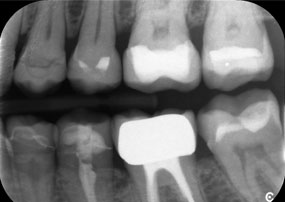

A jaw x-ray from an 81-year-old patient, in front of a black background.

Figure 1: Aesthetic rehabilitation of PFM crowns: Complete removal and replacement of 40-year-old PFM crowns to improve aesthetics in an 81-year-old patient.